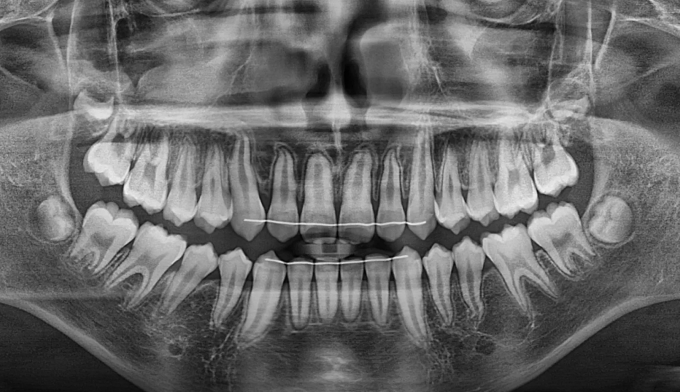

이번 케이스에서는 위쪽 송곳니의 맹출경로이상, 아래쪽 작은어금니는 작은 물혹으로 인해 맹출 경로에 문제가 생겨 교정을 진행한 경우입니다.

물혹을 제거하고 치아 교정장치를 부착하여 간단히 배열하였습니다.

총 교정기간은 11개월 입니다.